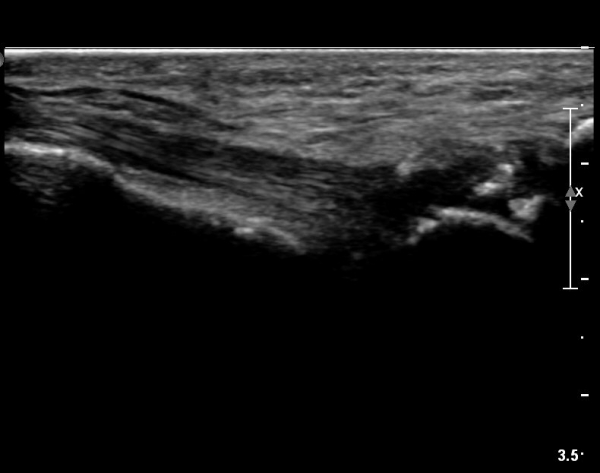

ÃÊÀ½ÆÄ °Ë»ç

±¹¼ÒÀû ¾ÐÅëÀ» º¸ÀÌ´Â ÁßÁ·°ñÀÔ¹æ°ñ °üÀý ¹Ù´ÚÃø¿¡ ŽÃËÀÚ¸¦ ´ë´Ï Á¾ÀÚ»ÀÀÇ °¡ µÎ Á¶°¢À¸·Î

°üÂûµÇ°í Á¾ÀÚ»À ±ÙÀ§ºÎ¿¡ Àú¿¡ÄÚ ¿¬ºÎÁ¶Á÷ ºÎÁ¾ÀÌ °üÂûµÇ°í µÎ Á¾ÀÚ»À »çÀÌÀÇ »À Ç¥¸éÀÌ °ÅÄ£

¾ç»óÀ» º¸ÀÓ(»çÁø 1).